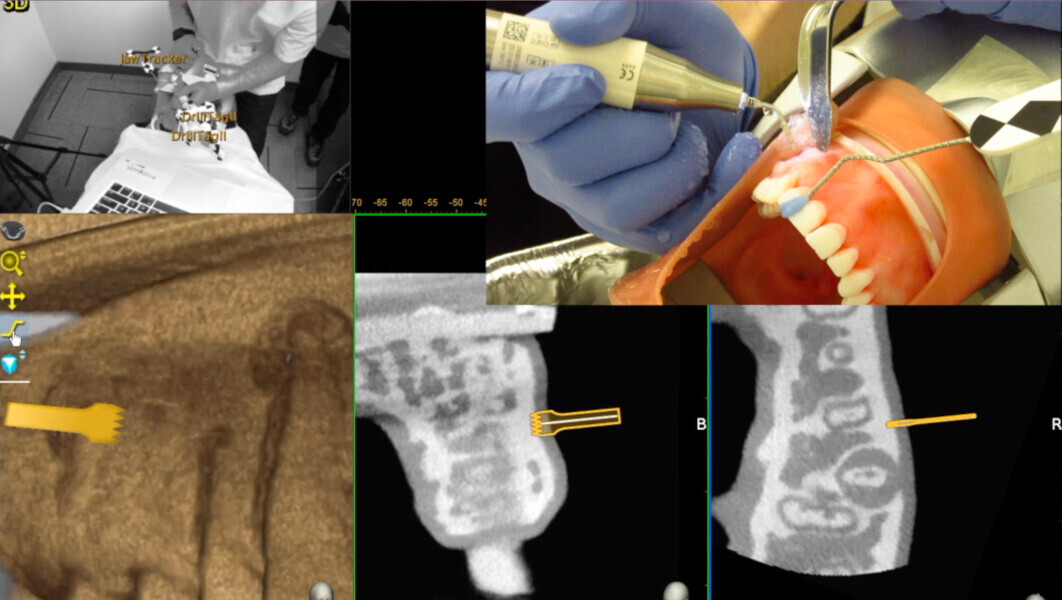

Fig. 2: An optical tracking sensor tracks the Jaw-Tracker, Tracer Tracker, Drill-Tracker and instrument.

Fig. 3: The screen is divided into (1) panoramic view, (2) 3D reconstruction, (3) axial view, and (4) buccolingual and (5) mesiodistal section views.